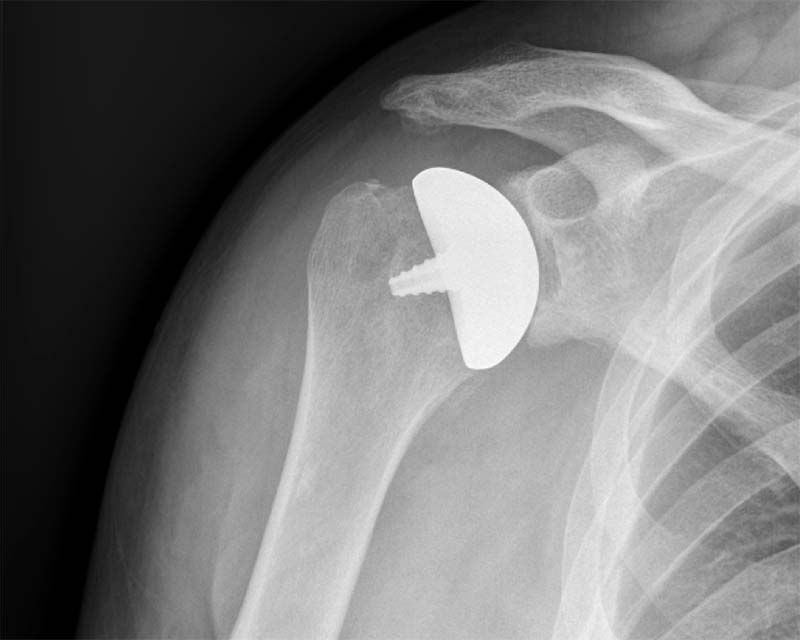

OVO / OVO MOTION

Sistemas de artroplastia total de hombro Inlay Glenoid

- Implantes en forma ovoide no esférico para coincidir con la anatomía de la cabeza humeral.

- Reduce el riesgo de sobre relleno manteniendo la estabilidad glenohumeral y la tensión de los tejidos blandos.

- Diseñado para abordar las clasificaciones glenoideas Tipo A, B y C.